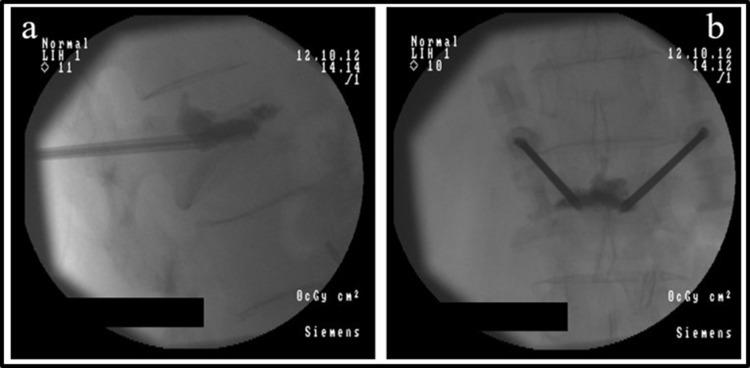

在患有癌症相关疼痛的患者中,10%至20%的患者按照世界卫生组织的三阶梯指南无法实现充分控制。因此,对于这些病例,有人建议采取包括介入治疗方法在内的“第四步”。系统评价支持早期使用介入程序来治疗难治性癌症疼痛、控制症状并防止阿片类药物剂量增加。有强有力的证据表明腹腔神经丛或内脏神经松解术、椎体成形术、后凸成形术和鞘内药物递送的有效性。已发现这些程序与症状负担减轻和阿片类药物消耗减少、生活质量改善相关,并且被认为对生存可能有积极影响。几项研究建议在更早阶段使用特定的介入技术,甚至可能在首次考虑阿片类药物治疗时就使用。相反,将这些选择留作最后的镇痛资源可能并不可取,因为这些程序可能给病情过重的患者带来的负担很大。本综述的目的是收集已发表的关于使用介入治疗难治性癌症疼痛的现有证据,特别关注比较早期与晚期适应症。检索结果显示专门针对这个问题的文章数量和质量都非常低。证据数量稀少,无法进行系统分析。本文提供了关于在疾病早期将介入技术纳入临床指南的潜在益处的详细叙述性描述。

Vertebral Augmentation of Cancer-Related Spinal Compression Fractures: A Systematic Review and Meta-Analysis.

癌症相关性脊柱压缩性骨折的椎体增强治疗:系统评价和荟萃分析。

Spine (Phila Pa 1976). 2021 Dec 15;46(24):1729-1737. doi: 10.1097/BRS.0000000000004093.

Preventive Vertebroplasty for Long-Term Consolidation of Vertebral Metastases.预防性椎体成形术治疗椎体转移的长期巩固。

Cardiovasc Intervent Radiol. 2019 Dec;42(12):1726-1737. doi: 10.1007/s00270-019-02314-6. Epub 2019 Aug 23.